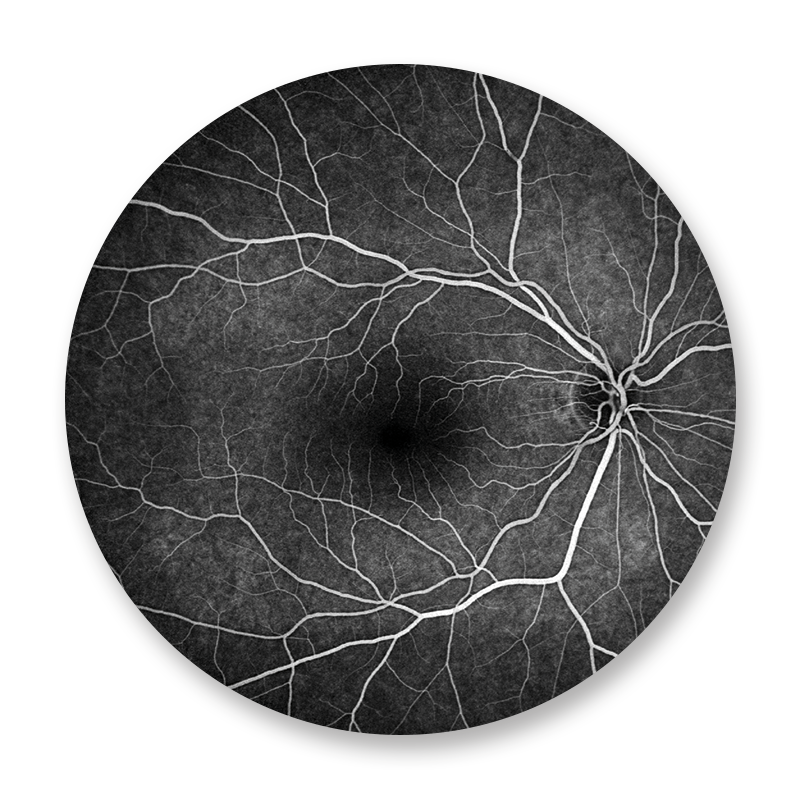

Der Augenhintergrund wird mit einer aufwendigen digitalen Kameratechnik fotografiert. Während der FAG wird zuerst eine Farbaufnahme und eine Autofluoreszenzaufnahme des Augenhintergrundes erstellt. Es folgt die intravenöse Gabe eines Farbstoffes, der sich in den Gefäßen der Netzhaut darstellt und dort krankhafte Veränderungen anzeigt. Die Fluoreszenzangiographie spielt eine wichtige Rolle bei der Beurteilung und Therapieplanung der altersbedingten Makuladegeneration, bei Gefäßverschlüssen, so wie bei der diabetischen Netzhauterkrankung.